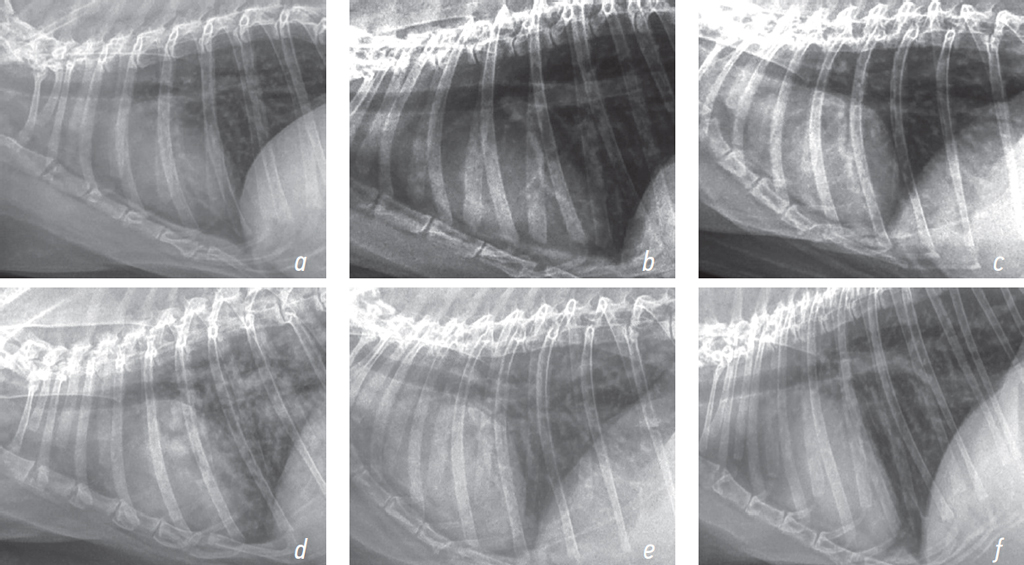

Plain chest radiography of rabbit 1 showed preserved lung fairness, normally visualized cardiovascular structures, smooth and clear diaphragmatic dome, and preserved cardiosternal contact. An hour after exposure, areas of interstitial shadowing and prominent bronchopulmonary pattern were noted on plain chest radiographs of rabbits 2 and 3 (Figs. 1 and 2).

Fig. 2. X-rays of the chest organs of rabbits in lateral projection at various times after exposure to the thermal destruction products of fluoroplastic-4 (1,5 HLC50); a — rabbit 1 (control), b — rabbit 2 (intoxication, 1 hour), c — rabbit 3 (treatment, 1 hour), d — rabbit 2 (intoxication, 6 hours), e — rabbit 3 (treatment, 6 hours), f — rabbit 3 (treatment, 7 days)

Рис. 2. Рентгенограммы органов грудной клетки кроликов в боковой проекции в различные сроки после воздействия продуктов термодеструкции фторопласта-4 (1,5 HLC50); a — кролик 1 (контроль), b — кролик 2 (интоксикация, 1 ч), c — кролик 3 (лечение, 1 ч), d — кролик 2 (интоксикация, 6 ч), e — кролик 3 (лечение, 6 ч), f — кролик 3 (лечение, 7-е сут)

Radiography was performed 6 hours following exposure. Plain chest radiography of rabbit 2 showed diffuse alveolar opacities, most prominent in the middle and caudal lobes, and notable bronchopulmonary pattern. Plain chest radiography of rabbit 3 showed a moderately prominent bronchopulmonary pattern and normal lung airiness (Figs. 1 and 2).

On day 7 after exposure, the gas exchange parameters (i. e., SaO2, PetCO2, and OI) in rabbit 3 did not differ from background values. Plain chest radiography demonstrated normal lung airiness with no areas of interstitial shadowing (Figs. 1 and 2). Auscultation revealed no wheezing. After radiography, rabbits 3 and 1 were sacrificed and their lungs were removed.